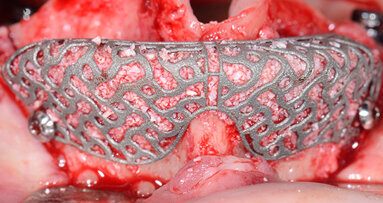

Oggi sviluppiamo piani di trattamento che non prevedono l’inserimento implantare sulla base della sola anatomia esistente ma anche sulla base delle ...